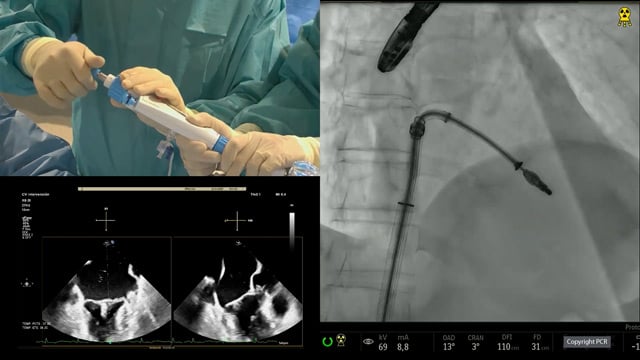

Real-world outcomes with the PASCAL Platform in TR

The PASCAL platform, comprising the PASCAL and PASCAL Ace implants, received its CE mark for TR in May 2020 and has been shown to be an effective and safe treatment option for patients with TR.3,4,6 Professor Jörg Hausleiter and Dr Mirjam Wild now describe their single-centre experience...